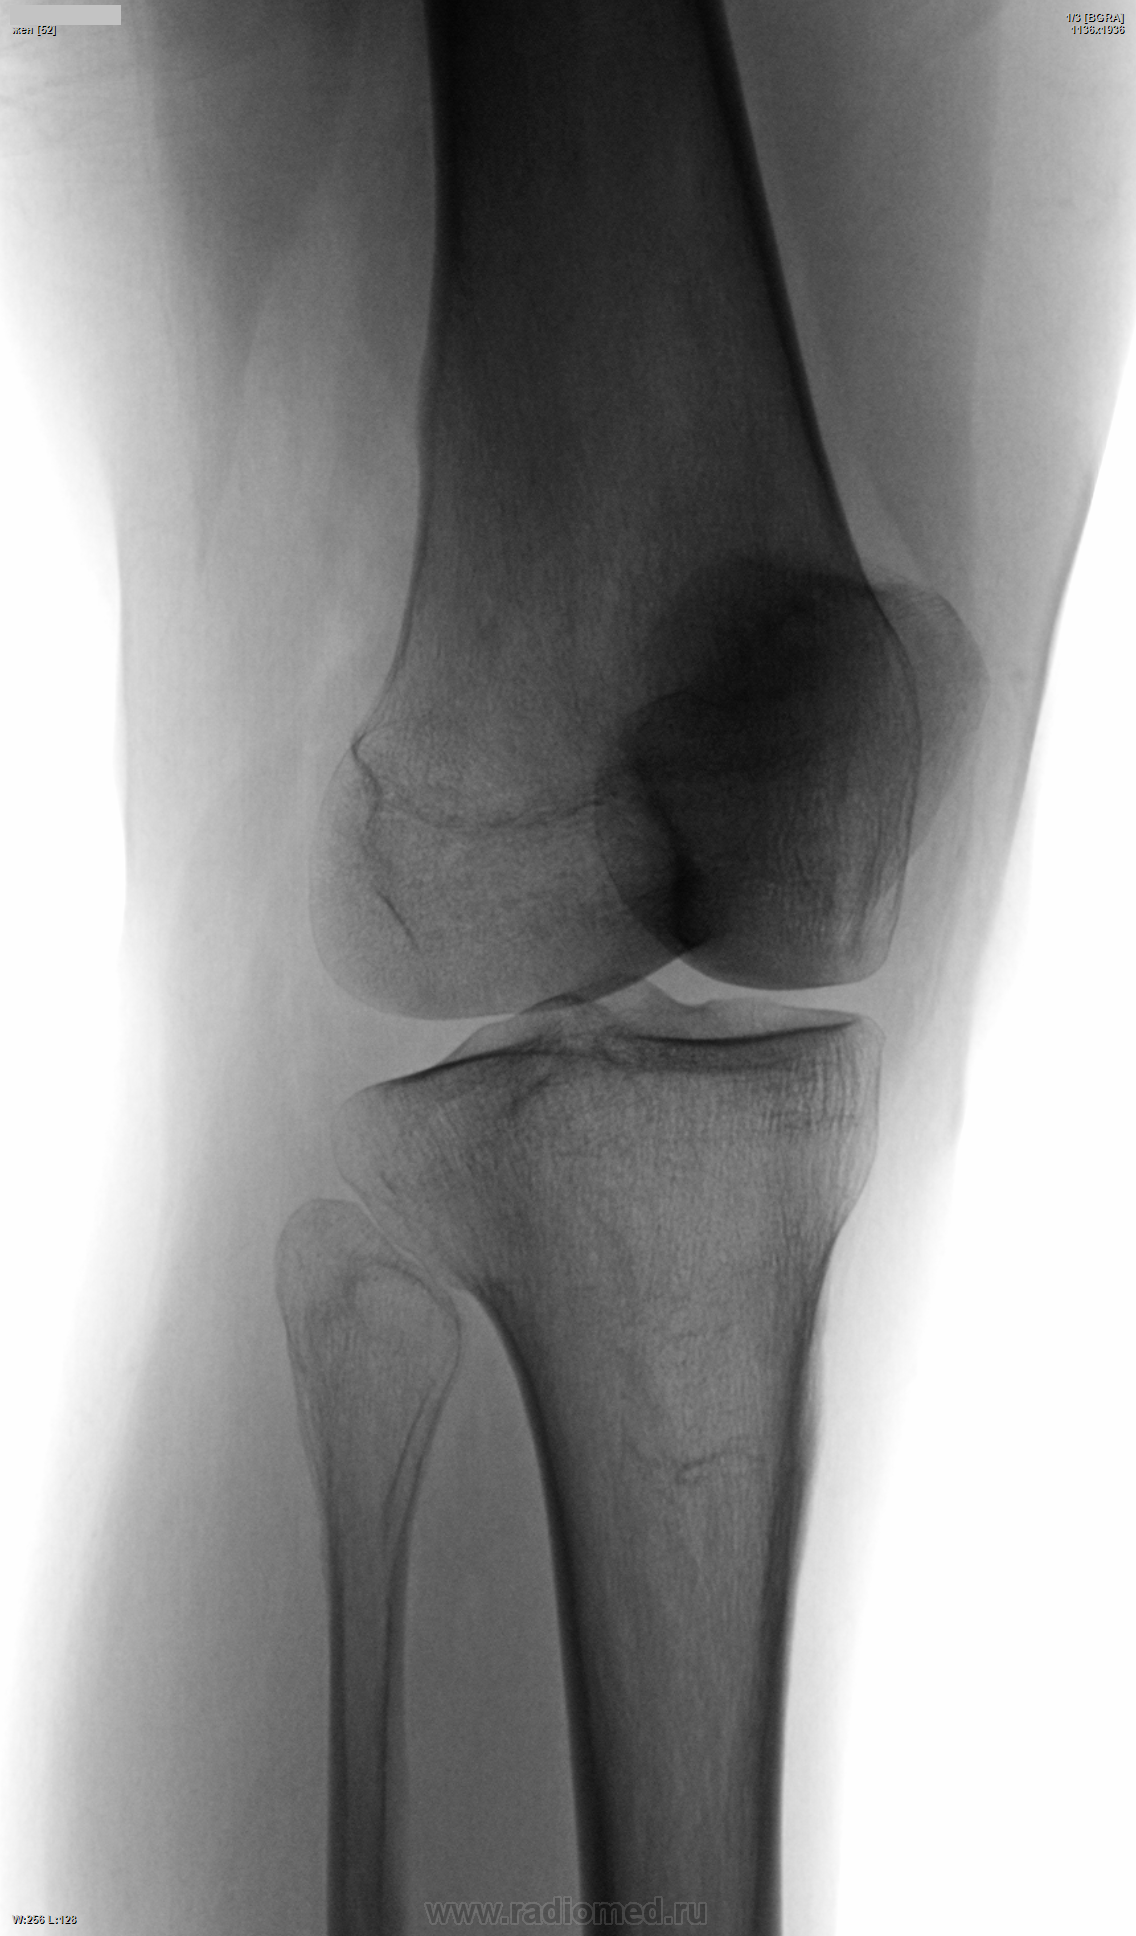

Пол пациента: Женский пол Тип патологии: ТравмаДругое Область исследования: Скелетно-мышечная система Методы исследования: Rg Женщина, 52 лет, с болями в колене. А у кого их сейчас нет? Смотрел на артроз, но увидел нечто иное. Коллеги, если не ново, как возможно такое?.. https://radiomed.ru/sites/default/files/styles/case_slider_image/public/user/4508/144_lst_0001.png?itok=MUEGHztB https://radiomed.ru/sites/default/files/styles/case_slider_image/public/user/4508/144-3.png?itok=g8aIPhgh ID:34356 Wed, 18/12/2013 - 19:07 #1 maker4ik Offline Last seen: 8 years 7 months ago Joined: 19.10.2011 - 17:49 Posts: 2682 Кроме артроза ничего не увидела. Wed, 18/12/2013 - 20:07 #2 Алексей Станисл... Offline Last seen: 5 years 10 months ago Joined: 11.08.2012 - 20:33 Posts: 1903 Кроме пателло-феморального (начального) артроза и тендиноза сухожилия квадрицепса, ничего не увидел. С уважением, Wed, 18/12/2013 - 21:16 #3 schlyapa Offline Last seen: 8 years 3 weeks ago Joined: 27.09.2013 - 22:15 Posts: 613 Экзостоз по передней пов-ти эпифиза м\б кости? Thu, 19/12/2013 - 00:46 #4 Алексей Игореви... Offline Last seen: 6 years 10 months ago Joined: 08.08.2012 - 21:52 Posts: 786 А что кроме артроза Вас смущает? Не вижу за что еще зацепится. "Обучая других - учишься сам". Н.И.Пирогов Fri, 20/12/2013 - 17:30 #5 Сан Саныч1 Offline Last seen: 12 months 1 hour ago Joined: 07.06.2010 - 21:17 Posts: 2114 Пателло-феморальный артроз І ст, тендиноз квадрицепса. Хочешь сделать что-то нормально - сделай это сам! Fri, 20/12/2013 - 23:06 #6 Дмитрий Волегов Offline Last seen: 3 years 6 months ago Joined: 22.05.2013 - 00:32 Posts: 1148 Возможно была травма латерального мениска в детстве. На МРТ, если нет анамнеза. С Уважением, Дмитрий. Sat, 21/12/2013 - 14:45 #7 Makcimalist Offline Last seen: 11 years 9 months ago Joined: 08.05.2010 - 14:28 Posts: 1994 schlyapa wrote: Экзостоз по передней пов-ти эпифиза м\б кости? Да, глаз прицепился к головке малоберцовой. Решил, что сломалась как-то - отломок призначился - доснял косую проекцию через пару дней я. Оказалось, тень (эностоз/перелом(?)) в большеберцовой сидит - и кто это он, о чём говорит?..Приложения: -------------- "Просто, по видимости, не видеть логики в очевидных вещах - это тоже одно из свойств некоторых умов, наряду с грустными думами о свойствах ума других." © Vega 08/10/2011

Кроме пателло-феморального (начального) артроза и тендиноза сухожилия квадрицепса, ничего не увидел.

Экзостоз по передней пов-ти эпифиза м\б кости?

Пателло-феморальный артроз І ст, тендиноз квадрицепса.

Возможно была травма латерального мениска в детстве. На МРТ, если нет анамнеза.

Да, глаз прицепился к головке малоберцовой. Решил, что сломалась как-то - отломок призначился - доснял косую проекцию через пару дней я. Оказалось, тень (эностоз/перелом(?)) в большеберцовой сидит - и кто это он, о чём говорит?..